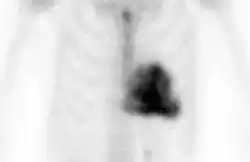

Amyloid deposition in aortic stenosis shown by DPD scan

A DPD scan is a type of nuclear medicine imaging test which uses radioactive technetium-99m (99mTc) and 3,3-diphosphono-1,2-propanodicarboxylic acid (DPD) to diagnose cardiac amyloidosis. The radiopharmaceutical is taken up only in patients with ATTR amyloidosis, making it a useful tool to differentiate from AL amyloidosis.[1]